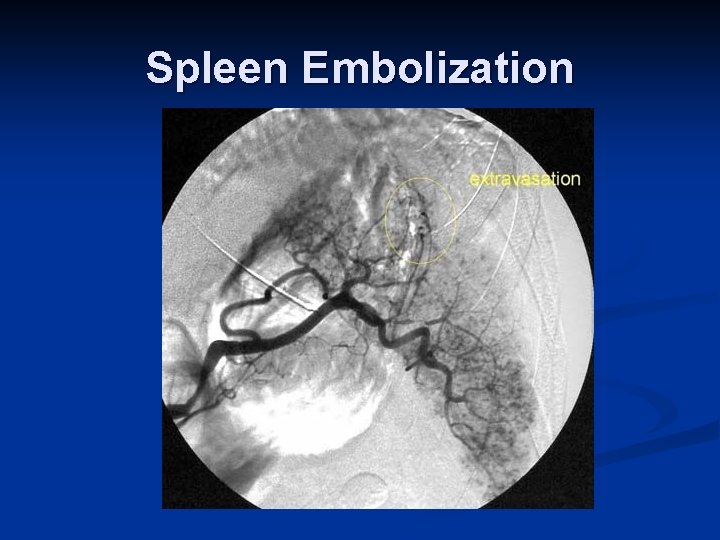

Role of Interventional Radiology n Embolization Spleen n Liver n Pelvis n n Angioplasty + Stent n n Renal artery dissection Stent n Thoracic aortic injuries

Spleen Embolization